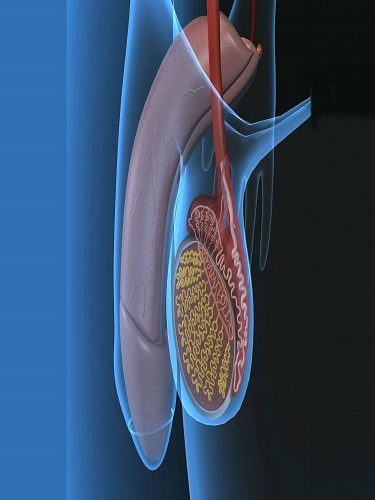

– OVER KİST AMELİYATI (YUMURTALIK KİSTİ AMELİYATI) (OVER KİSTEKTOMİ) Hemen her kadında hayatını belirli bir döneminde over kistlere rastlanabilmektedir. Bu kistlerin farklı tüpleri bulunmaktadır. Bu çeşitliliğe uygun tedavi yöntemleri de bulunmaktadır. Over kistlerinde en sık rastlanan şikayetler cinsel ilişki sırasında ağrı, kasık ağrısı, karında şişkinlik veya basınç hissi ve adet düzensizlikleridir. Yumurtalık (over) kistleri her…